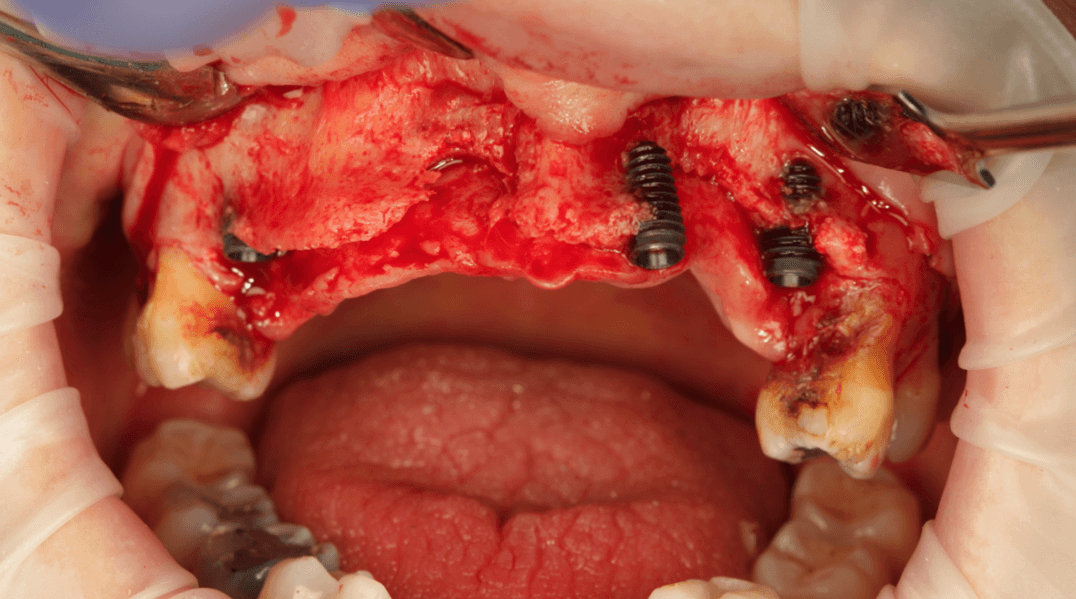

A true clinical residency where you plan, assist, and perform real full-arch surgeries under the guidance of Dr. Pedro Rodrigues and his team. Gain the confidence and skills to elevate your practice.

Exclusive 1-on-1 training where you perform 4 full-arch surgeries (2 as main surgeon and 2 as assistant) under Dr. Pedro Rodrigues’ direct supervision.

Gain hands-on experience performing full-arch surgeries under the direct supervision of Dr. Pedro Rodrigues.

Hands-on training: operate 4 full-arch surgeries (2 as main surgeon and 2 as assistant) with Dr. Pedro Rodrigues

Operate 4 full-arch surgeries (2 as main surgeon and 2 as assistant) under supervision

Advanced cases: from challenging to extreme